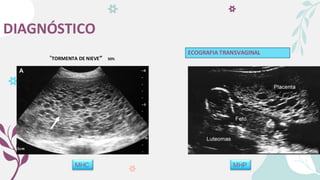

DIAGNÓSTICO

MHC MHP

ECOGRAFIA TRANSVAGINAL

“TORMENTA DE NIEVE” 50%